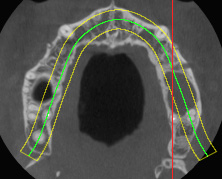

Проанализированы 96 CD-дисков пациентов с данными КЛКТ и МСКТ верхней челюсти из базы архива ГБУЗ СК «ПГКБ», РКБ им. Вишневского, г. Махачкала, ГБУЗ СК «СККБ», г. Ставрополь, БСМП № 1, г. Ростов-на-Дону, с 2010 по 2024 г. В исследование включены пациенты, которым осуществлены два метода исследования: МСКТ и КЛКТ при наличии рентгенограмм. Основной причиной выполнения двух методов диагностики являлась недостаточная информативность одного из них. МСКТ 48 пациентам выполнена на аппарате Toshiba Aquilion CXL 128 c интерпретацией в программе Radiant 3.0, 2023, исследование назначалось по тем или иным причинам специалистами нестоматологического профиля. Рентгенологи после случайных «находок» направляли пациентов на консультацию стоматолога или челюстно-лицевого хирурга. Дефицит информации по данным МСКТ являлся основанием для выполнения 48 КЛКТ-исследований. КЛКТ выполнены на аппарате Planmeca ProMax 3DClassic c последующим прочтением в программе Planmeca Romexis Viewer Win. Объем верхнечелюстных пазух измеряли с детализацией высоты, глубины и ширины синусов, что позволяло детализировать тип пневматизации и симметричность пазух. Сравнивали пристеночные соединительнотканные структуры, определяя высоту и толщину кости в проекции отсутствующих зубов виртуальной линейкой с определением длины корней зубов и расстояний от анатомической верхушки корня до дна ВП.